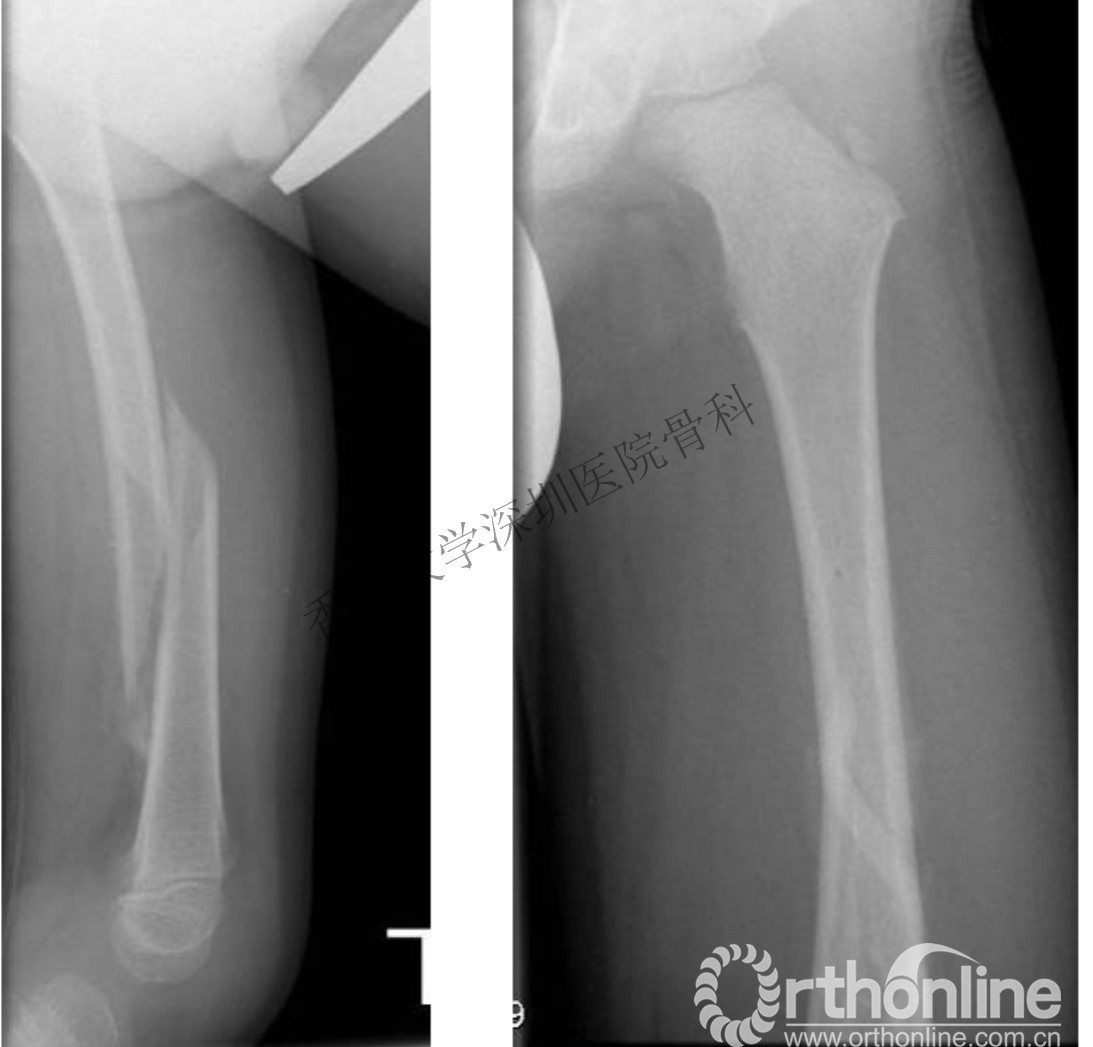

2岁儿童骨折,受伤时和1年后对比,塑型良好(受伤时)

2岁儿童骨折,受伤时和1年后对比,塑型良好(受伤1年后)

同时,我们也应该注意避免过度治疗,因为儿童骨骼具有良好的塑形能力,有时候并不需要解剖复位,很多对于成人无法接受的骨折移位,也可以得到良好的愈合和重塑。

双下肢截骨矫形内固定术后,畸形得到良好纠正。